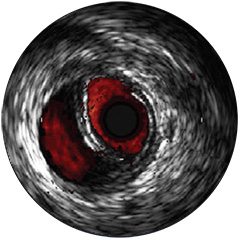

IntraSight ist auf Basis einer intelligenten, anwendungsbasierten Plattform konzipiert, die sich bei neuen verfügbaren Anwendungen und Modalitäten an die sich ändernden Anforderungen Ihres Labors anpassen lässt – und das ohne neue Hardware erwerben zu müssen. Nur IntraSight von Philips bietet Ihnen erstklassige Bildverarbeitungs- und Physiologie-Tools mit iFR, iFR-Koregistrierung*, FFR, IVUS, IVUS-Koregistrierung* und Angio+*. Dank seiner modularen Architektur bleibt IntraSight über die neuesten Entwicklungen und wichtigen Sicherheitsupdates auf dem Laufenden.

Abbildung 3